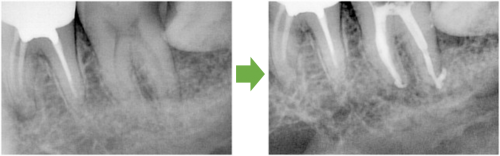

抜髄 左下の奥歯 川口の歯科 歯医者 さかえ歯科クリニック

2014年12月16日

川口の歯科 歯医者 さかえ歯科クリニック